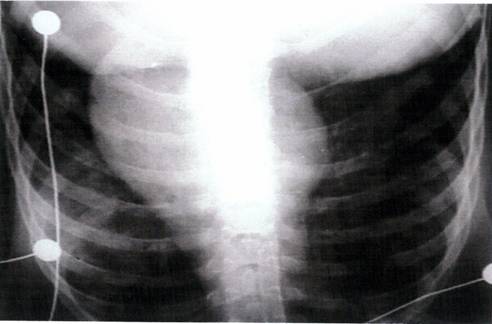

Marirea siluetei cardiace poate fi normala in radiografia toracica simpla la pacientii cu cord pulmonar, dar in stadiul avansat, inima poate prezenta o rotatie anterioara si butonul aortic devine mai putin proeminent.In plus deoarece VD se extinde anterior si catre stanga va ocupa spatiul retrosternal.In plus deoarece VD va forma cea mai mare parte a arcului cardiac stang, fortand VS sa se pastreze posterior si conferind inimii stangi un aspect lobular.

In radiografia toracica simpla hipertensiunea pulmonara este indicata de dilatarea trunchiului arterei pulmonare si a ramurilor sale cu stergerea desenului vascular periferic.Intr-un studiu la pacientii cu BPOC masurarea celui mai mare diametru al arterei pulmonare (presiunea arteriala pulmonara medie >20 mmHg).

Un alt studiu la pacientii cu BPOC cu diametru arterei pulmonare drepte ≥20 mm a separat pacientii cu hipertensiune pulmonara de cei fara.Raportul cardiotoracic hilar a fost un index mult mai sensibil: 95% pentru hipertensiunea arteriala pulmonara la pacientii cu BPOC.Desi aceste masuratori pot indica prezenta hipertensiunii pulmonare, ele nu pot evalua valoarea si severitatea acesteia.(Fig.8).

FIG.8 Radiografia toracica simpla.